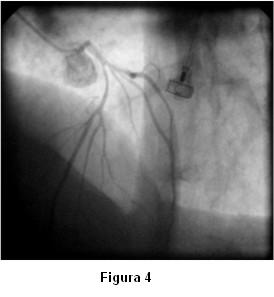

Con el planteo de síndrome coronario agudo de alto riesgo se solicita cineangiocoronariografía que muestra arterias coronarias sin lesiones significativas. Durante el estudio, al momento de cateterizar la coronaria izquierda, se observa severo vasoespasmo de las arterias descendente anterior, circunfleja y sus ramos secundarios (figura 4) con reproducción de los síntomas, que revierte espontáneamente en la siguiente inyección (figura 5).

Antes de la finalización del estudio de la coronaria izquierda reitera espasmo (figura 6) que mejora sin necesidad de administración de vasodilatadores (figuras 7 y 8).

Lo particular del caso presentado fue la aparición de severo espasmo difuso y multivaso de forma espontánea al momento de la cateterización de la arteria coronaria izquierda, sin provocación farmacológica y con reversión también espontánea.